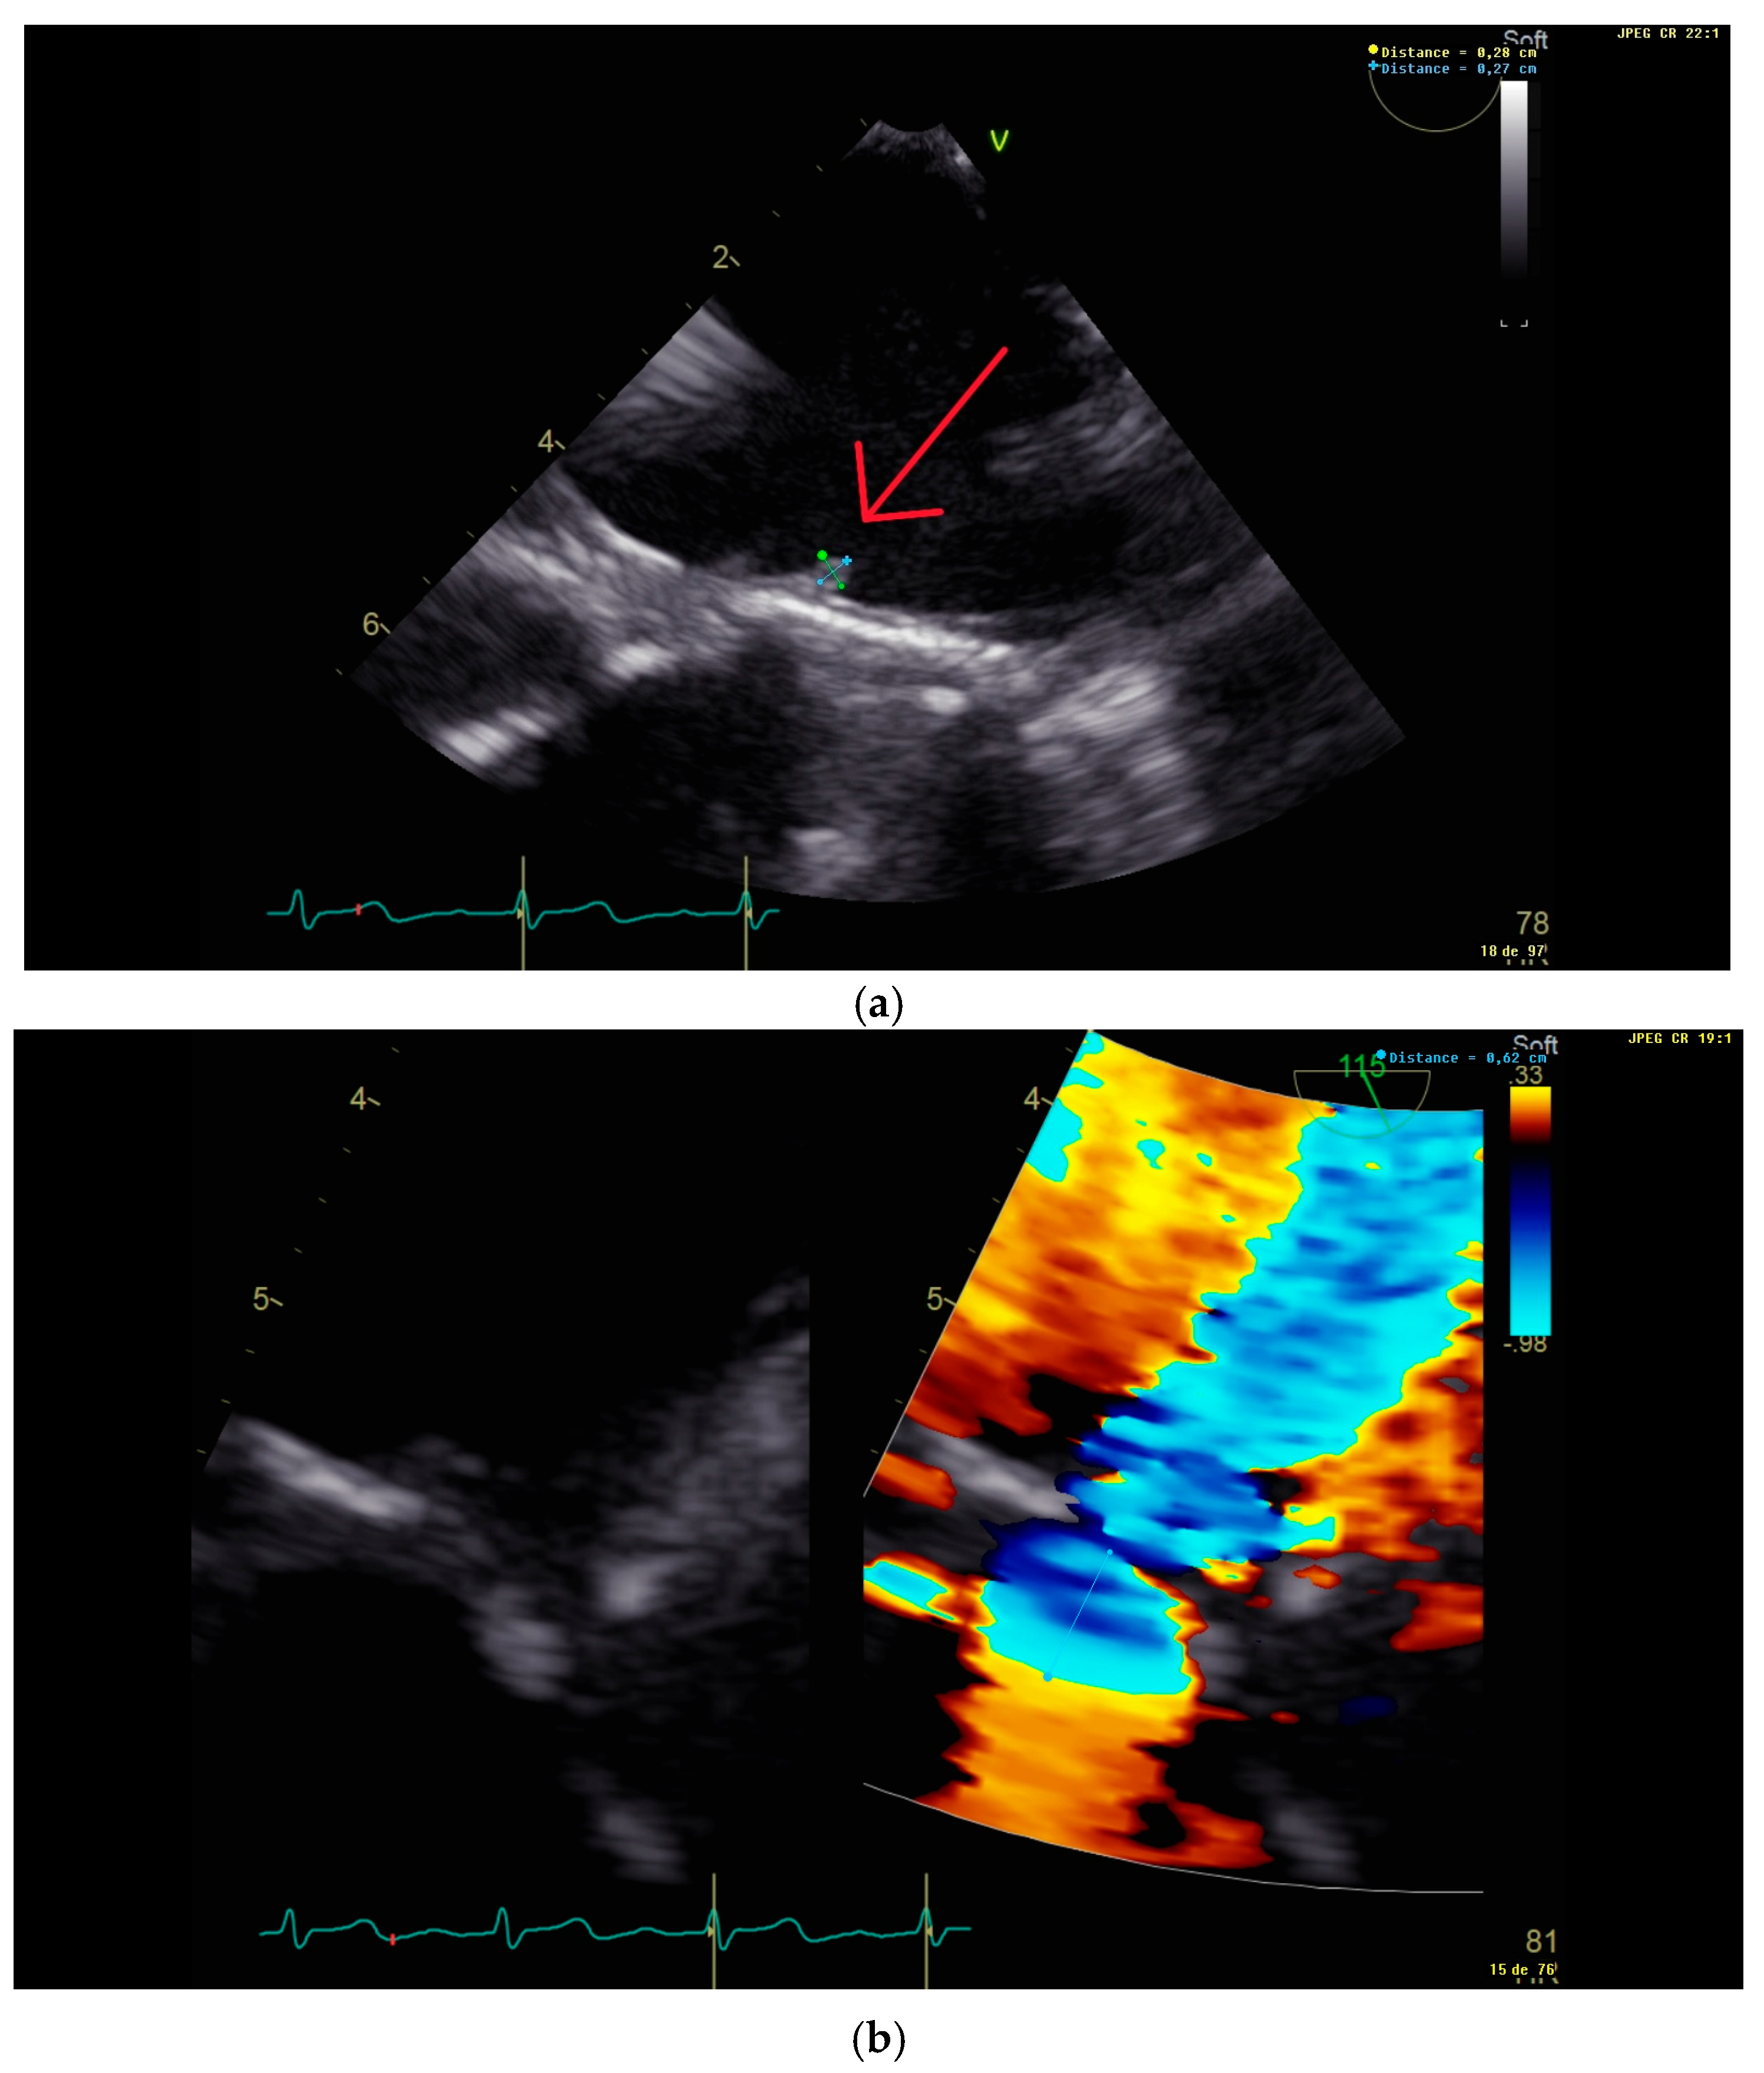

2. Case Presentation